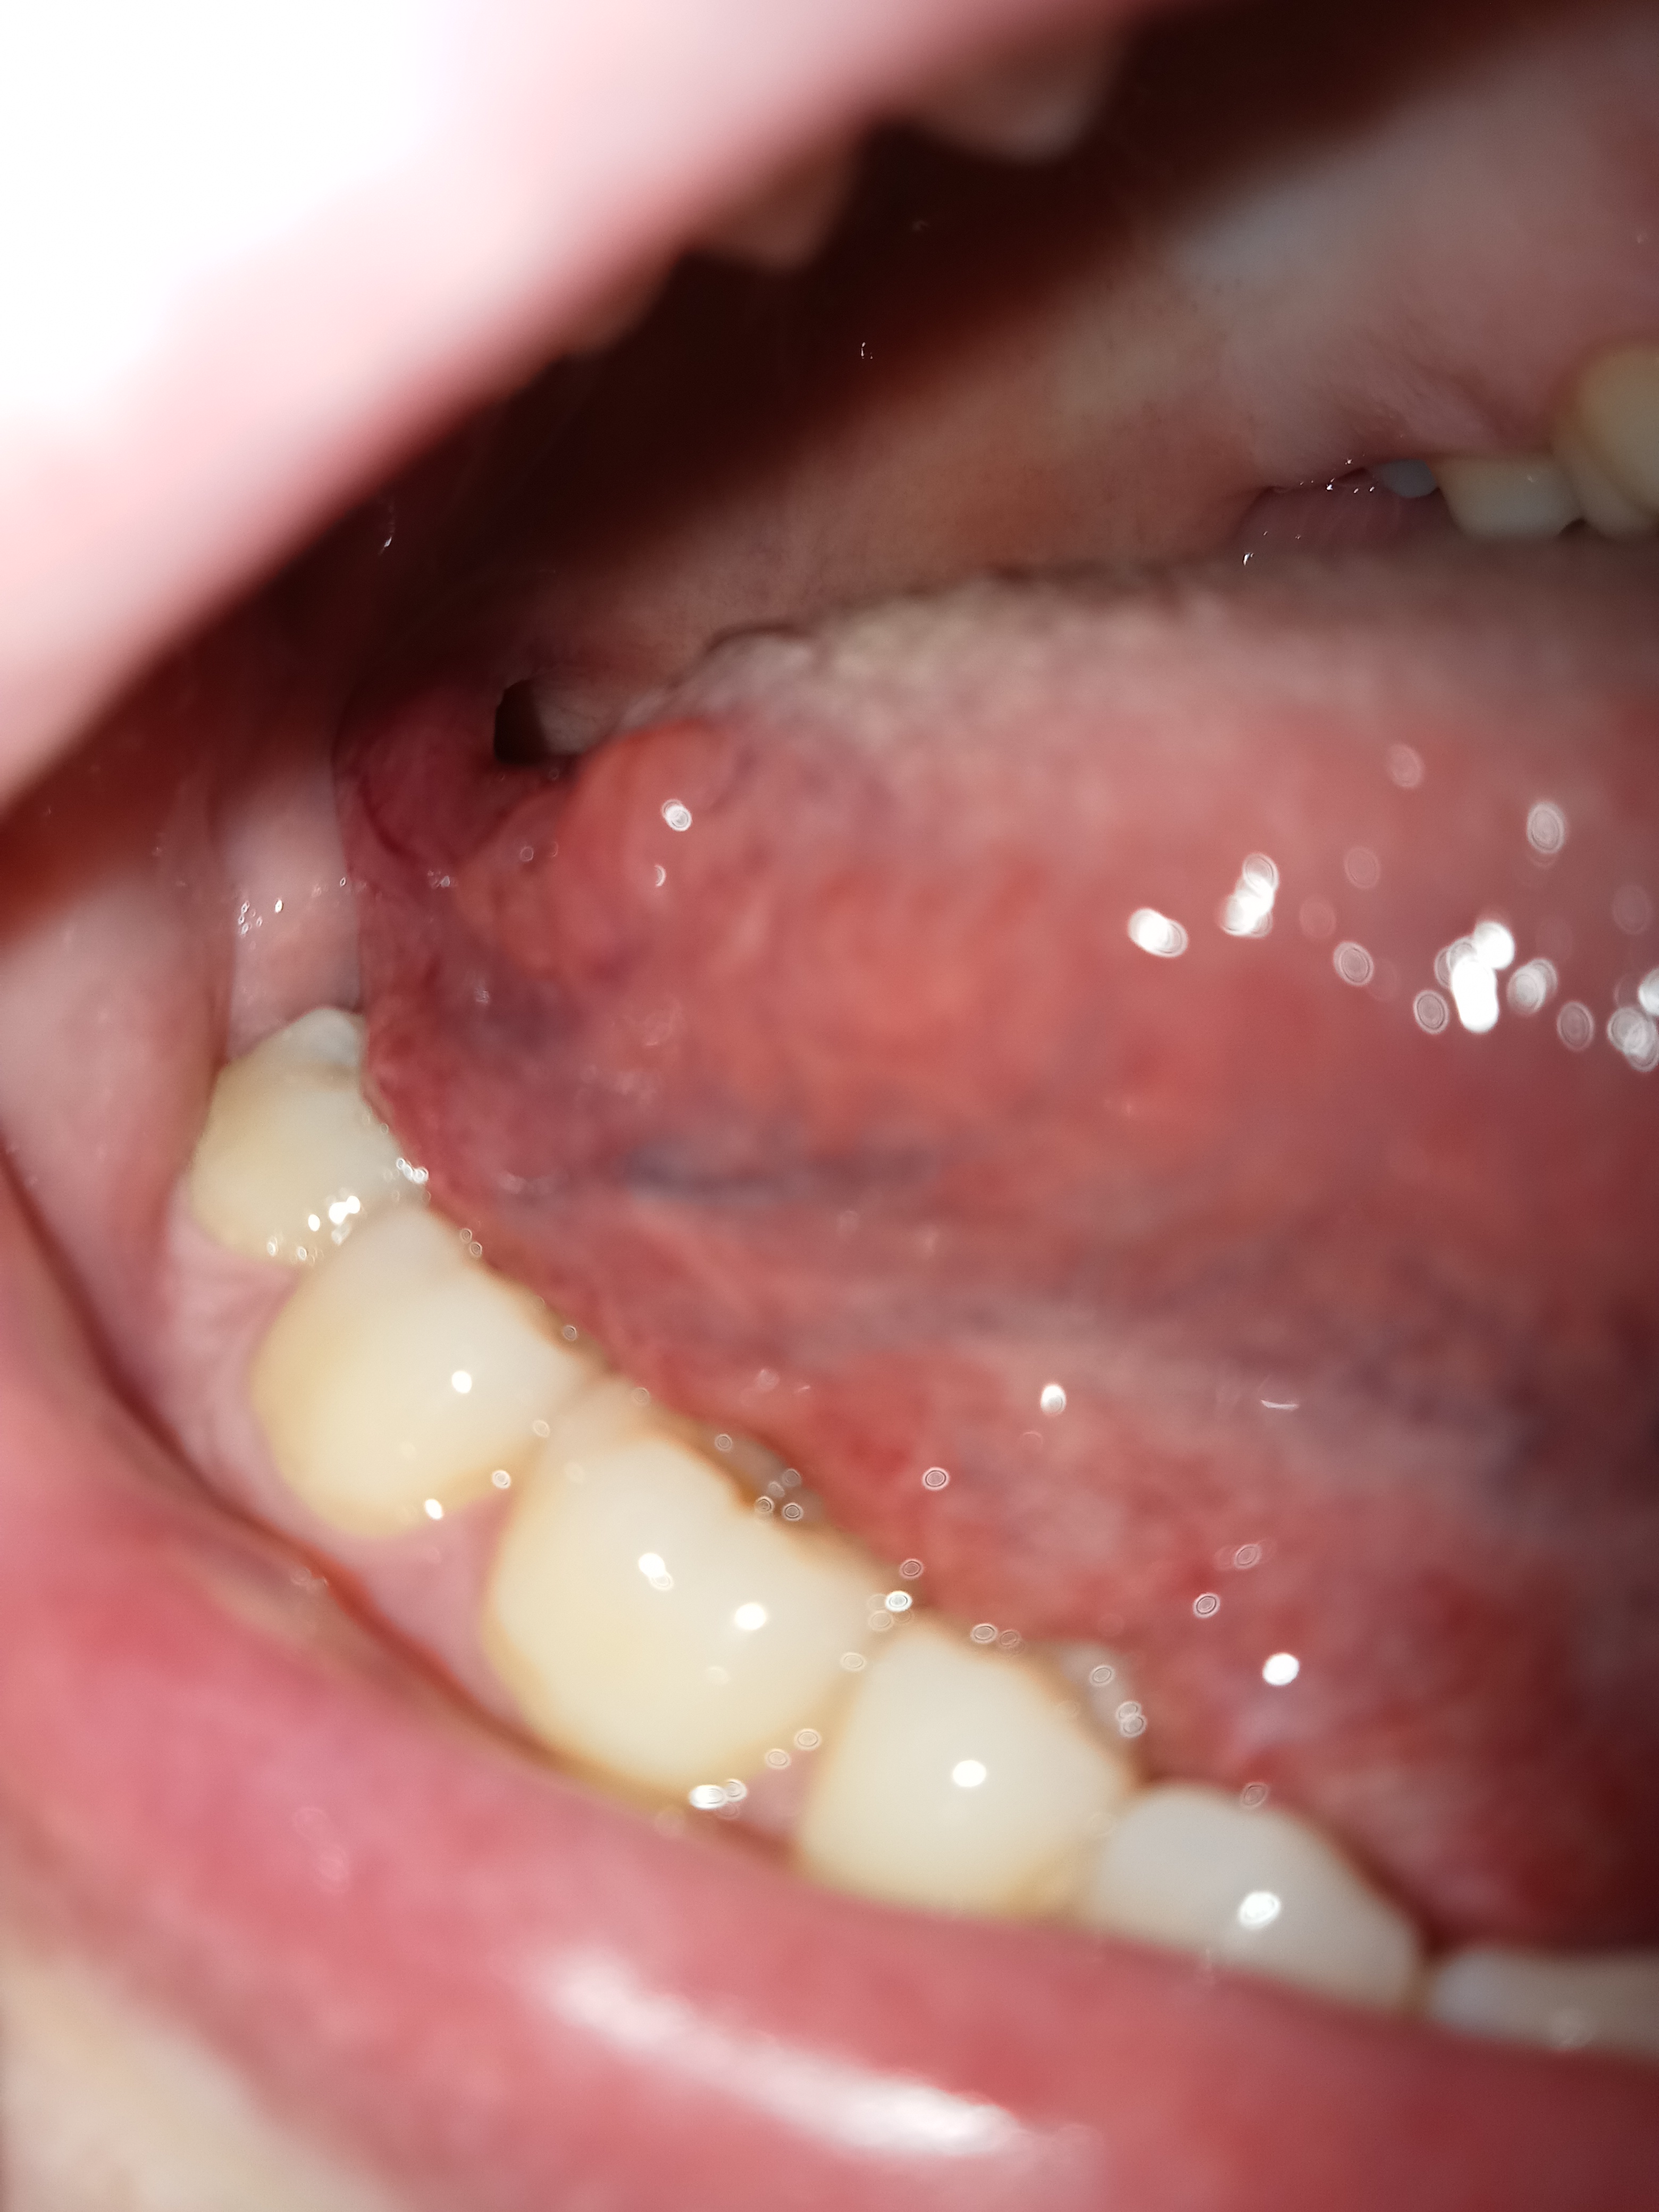

ich habe seit ca. 8 Monaten eine Veränderung der rechten hintern Zungenseite ( Zungengrund). Mit dieser war ich bereits bei meiner Zahnärztin vorstellig. Diese konnte mir jedoch nicht sagen was es ist und bat mich einen HNO oder MKG aufzusuchen. Ich habe beide nun bereits aufgesucht. Der HNO (welcher mich seit Jahren wegen chron. Sinusitis behandelt) meinte es seien Hypertrophe Ausläufer der lateralen Zungenmandel aber konnte mir auch nicht sagen wieso. ( Vl. wegen meiner Corona Erkrankung welche ich ca. 4 Wochen vor dem ersten bemerken der Veränderung hatte). Der MKG in der Praxis schaute kurz drauf und meinte hätten alle Menschen seien Papillen. Ich selbst merke an der Stelle seit ca 8 Monaten ein komisches Gefühl ( wie ein Fremdkörper) und wenn ich manschmal mit den Fingern drüber fahre habe ich einen bitteren Geschmack im Mund.Die Symptome sind mal mehr mal weniger. Meine Zahnärztin schickte mich nachdem ich 2 unterschiedliche Aussagen hatte in eine MKG einer UNI Klinik. Dort schauten es sich 2 Ärzte an und der Leitende Oberarzt dort meinte , rein optisch eher nicht maligne aber er würde mir es sicherhaltshalber operativ entfernen und dann eine Hysto. mitmachen. Mein HNO riet mir jedoch von der OP ab der meinte , es sind Tonsillen welche dann stark bluten würden und die Entzündungsgefahr sei sehr hoch. Nun bin ich völlig verunsichert was ich tun soll. Auf der einen Seite habe ich immer noch ein wenig Angst das es ein malignes Zungenkarzinom sein könnte , auf der anderen Seite habe ich auch Angst vor einer evtl unnötigen OP und das danach noch schlimmer alles ist. Was seit ca. 1 Monate neu ist das sich diese Veränderung oben am Ansatz gelb verfärbt. Denken Sie ist könnte maligne sein oder eher was benignes?

Ich wäre Ihnen sehr zum Dank verpflichtet wenn Sie sich kurz meine mitgeschickten Bilder anschauen könnten und mir Ihre Meinung dazu sagen würden.